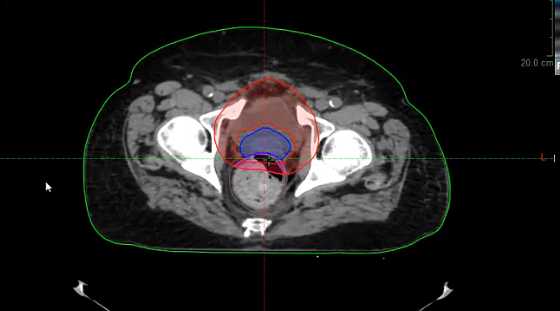

Gleason 6, Low Risk, Watchful waiting, SBRT toxicity, SIB, bladder cancer, low pelvis, hypofractionation, defining target, PSMA, prostate cancer, pT3aN0M0, rpT3acN1M0

Gleason score, active surveillance, periodic biopsy, prostate gland, pelvis, SIB, radiation-induced fibrosis, brachial plexus, head and neck, scleroderma, SBRT, TNM staging, bladder cancer, ASTRO, PSMA PET imaging, salvage prostatectomy, PSA

ADT, androgen deprivation therapy, LHRH antagonist, PSMA PET scan, definitive radiation, local salvage treatment, salvage brachytherapy, prostate cancer, PSA, genomic testing, brachytherapy, Gy, lymph nodes, pelvis, high risk intact patients, pelvic radiation, Mack Roach trials, salvage SBRT, loc...

urethral tumor, urothelial carcinoma, PET, CT, palliative treatment, mediastinal nodes, biopsy, prostate gland, PSMA, false positive, pelvis with nodes, bone lesions, PSA, bladder